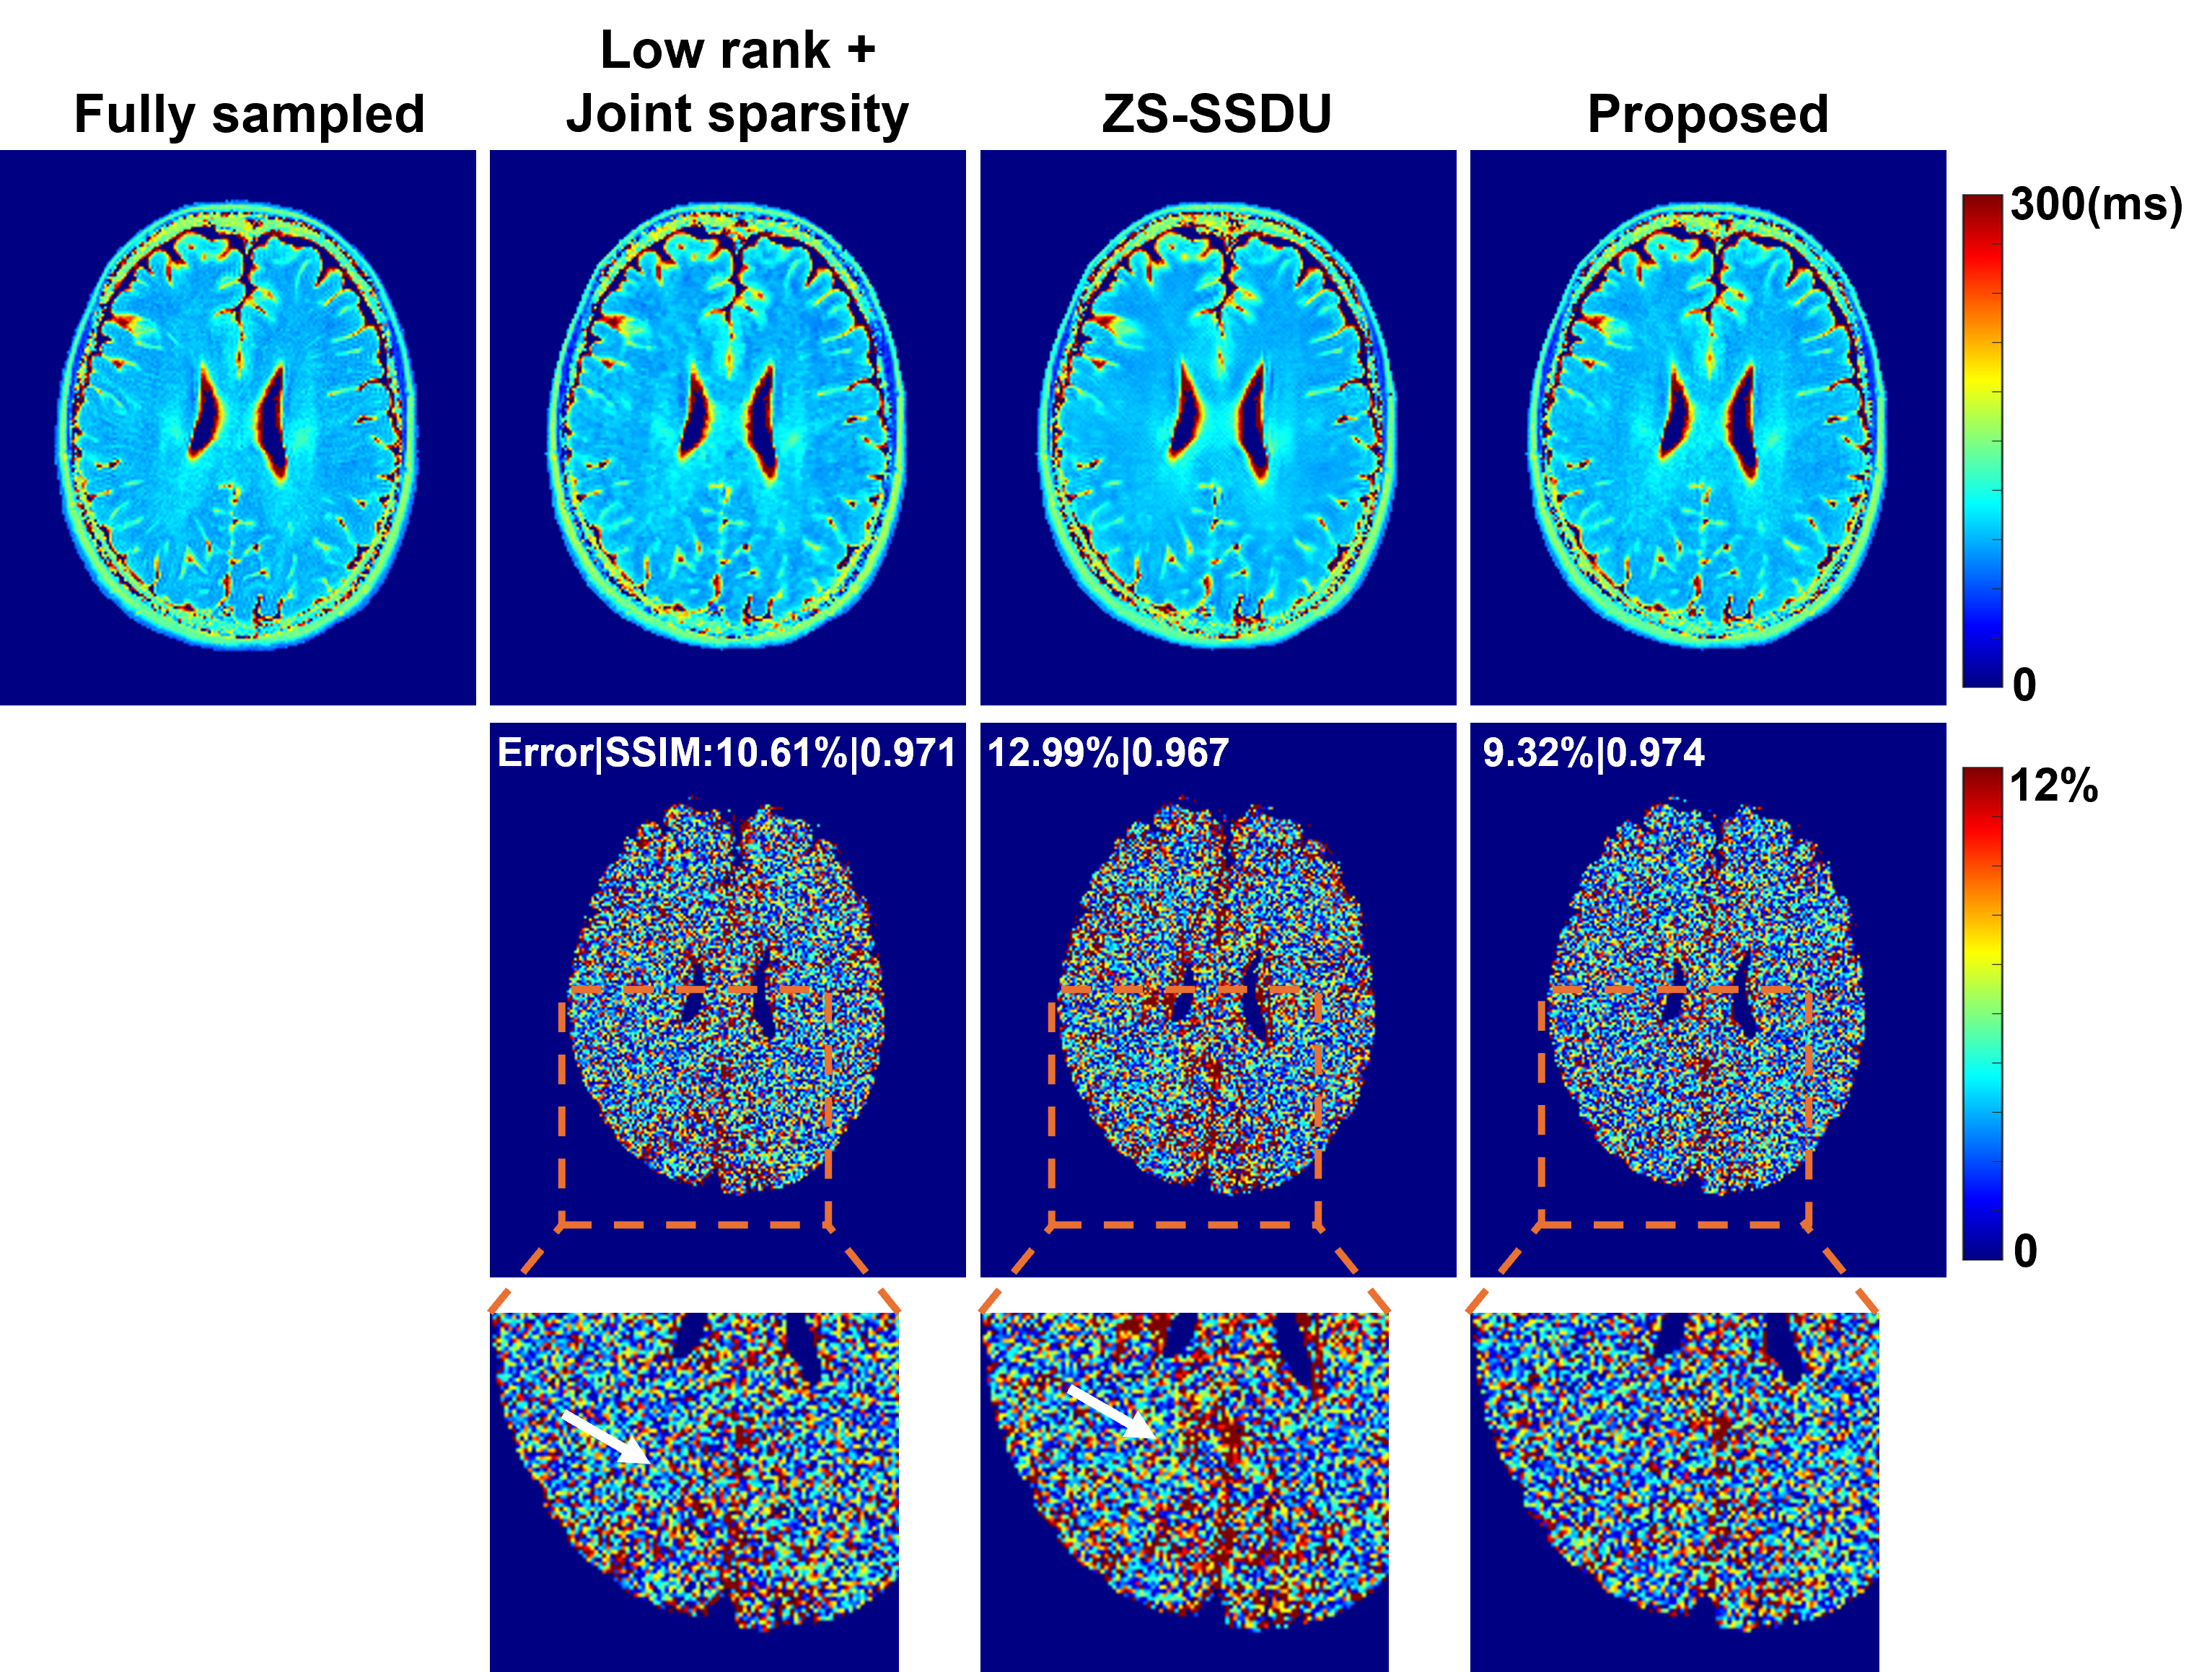

For $`\text{T}_1`$ mapping, we compared the proposed method with a joint sparsity constrained reconstruction and a state-of-the-art zero-shot self-supervised reconstruction method (ZS-SSDU) . We selected ZS-SSDU as a primary baseline because our method also follows a zero-shot learning paradigm, requiring no supervised re-training or fine-tuning on domain-specific datasets. Representative reconstructed images at AF=6 are shown in Fig. 4. The proposed method consistently produced reconstructions with improved quality and reduced errors across different contrasts (FAs) compared to other methods. The corresponding $`\text{T}_1`$ maps are shown in Fig. 5. The proposed method achieved the most accurate $`\text{T}_1`$ estimates w.r.t. the fully sampled reference as shown by the lowest relative $`\ell_2`$ errors and highest SSIM values, effectively suppressing artifacts. The zoomed-in regions further demonstrate a better preservation of structural details by the proposed method. The ZS-SSDU method, although produced lower errors than the joint sparsity method, seemed to result in strong bias in certain localized areas (Fig. 5, last row). These results demonstrated that the proposed representation can work synergistically with zero-shot self-supervised learning, leading to improved reconstruction and quantification performance. More quantitative comparisons under different AFs are shown in Fig. 7.

Fig. 6 compares $`\text{T}_2`$ mapping results estimated from reconstructions produced by different methods at AF = 8. The overall estimation errors and SSIM values w.r.t. the fully sampled data were computed within the brain regions with $`\text{T}_2`$ values lower than $`500`$ ms. The proposed method integrating our disentangled representation and subspace modeling yielded superior performance over a subspace reconstruction method with joint sparsity regularization and the ZS-SSDU method. These results also demonstrated the flexibility of the proposed representation to be combined with complementary constraints. Fig. 7 further demonstrates lower reconstruction errors consistently achieved by the proposed method across different AFs.